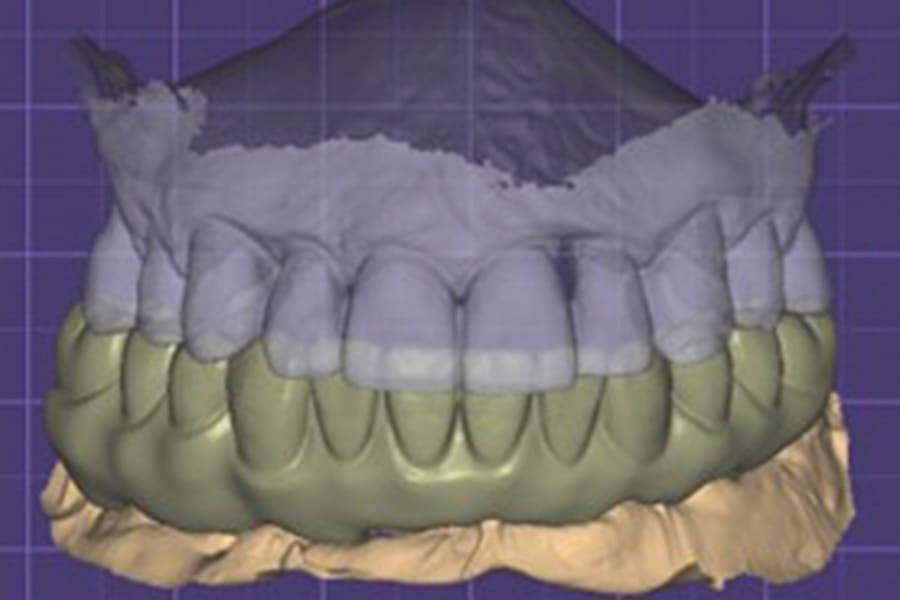

The intraoral scans were imported into DTX Studio software (DEXIS) to begin the implant and prosthesis planning (Figures 2 and 3). A virtual prosthesis was designed to articulate with the maxillary dentition (Figure 3). Implants were planned at four sites in the mandibular arch (Figure 1).

The previous virtual-designed prosthesis was merged with the scan of the implants. Modification of the hybrid design was accomplished creating the intaglio surface related to the implant connections and soft tissue (Figures 6 and 7). Emergence of the screw-access holes on the occlusal surface allowed sufficient prosthetic material around them to prevent fracture of the prosthesis during function (Figure 7). The virtual implant analogs were removed virtually, and the prosthesis design was completed in preparation for printing (Figure 8 through Figure 10). The hybrid prosthesis was printed on the Pro 55 S printer, utilizing OnX Tough 2.0 resin. Following 3D printing, the prosthesis was removed from the build plate with its supports present (Figure 11). The supports were removed with an acrylic bur and the surfaces were finished (Figures 12 and 13). Akzent LC gingival tone resin (VITA North America) was applied to the gingival aspects of the hybrid prosthesis and cured to provide a natural esthetic appearance.